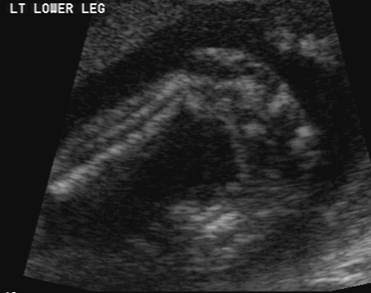

Imaging technique and findings ultrasound. Five cases of congenital clubfoot diagnosed prenatally by ultrasound are reported. Congenital talipes equinovarus is considered the most common anomaly affecting the feet diagnosed on antenatal ultrasound. The addition of microarray studies may increase the yield of invasive prenatal testing, although the complex inheritance patterns of clubfoot suggest that it rarely occurs due to a single gene mutation. 44% of fetuses underwent invasive diagnostic testing. Approximately 10% of all clubfeet can be diagnosed by 13 weeks gestation, and about 80% can be diagnosed by 24 weeks gestation. Although clubfoot is diagnosed at birth, many cases are first detected during a prenatal ultrasound. Ility of the ponseti method in correcting clubfeet; Once the child is born, the condition is clearly visible. Clubfoot can also be diagnosed by a doctor immediately after a baby is born. About 10 percent of clubfeet can be diagnosed as early as 13 weeks into pregnancy. Clubfoot may also result from a restricted environment in utero, such as from prolonged oligohydramnios or with abnormalities of the uterus that limit expansion of the gestational sac. Prenatal diagnosis of clubfoot is made sonographically when the bones of the foot lie in the same planes as the bones of the lower leg (figure 1).

In a fetus with clubfoot, the long axis of the foot (the sole) and the tibia can be seen in the same plane on ultrasound. However, diagnosis based on ultrasound alone produces a 20% false positive rate. Clubfoot is present in approximately 1 in 1000 live births in the united states. As many as four children out of every 1,000 are born with clubfoot. About 50 percent of children with clubfoot have it in both feet, a condition known as bilateral clubfoot.

It's possible to clearly see most cases of clubfoot before birth during a routine ultrasound exam in week 20 of pregnancy. Clubfoot can be diagnosed by ultrasound (sonogram) examination before birth. However, diagnosis based on ultrasound alone produces a 20% false positive rate. Common finding in trisomies 18 and 13. In examination of clubfeet, neurological status of the feet should be carefully assessed. We were quite surprised when we found out about the problem because it can be a hereditary thing and in the last 3 generations in both of our families there were no such issues reported. My mfm said the rest of the scan was normal. In clubfoot, the tissues connecting the muscles to the bone (tendons) are shorter than usual. The condition is normally identified after birth, but doctors can also tell if an unborn baby has. In about half of the children with clubfoot, both feet are affected. Clubfoot is present in approximately 1 in 1000 live births in the united states. Clubfoot causes the front of the foot to turn inward and the heel to point down. Clubfoot and positional foot deformities (eg, pes spinatus) may have the same aspects on prenatal ultrasound (us) imaging.